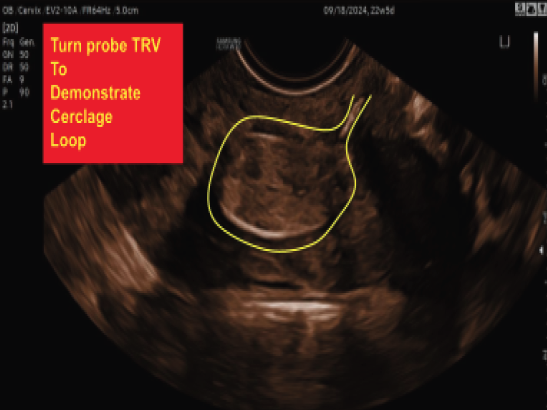

McDonald Cerclage: The McDonald cerclage is the most common procedure. It involves placing a stitch around the cervix, essentially creating a supportive loop that holds the cervix closed.